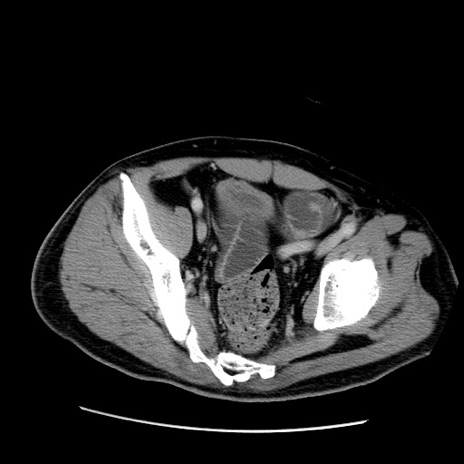

症例22(横断像)

【症例】50歳代男性

【主訴】腹痛

【現病歴】AVMからの被殻出血のため回復期リハ病棟入院中。 本日午後3時頃急に下腹部痛が出現した。

【既往歴】AVM、被殻出血、虫垂炎、高血圧

【身体所見】意識晴明、左半身不全麻痺、会話の理解は良好、36.5°C、腹部:膨隆、全体に板状硬、下腹部正中に圧痛点あり、反跳痛-、筋性防御不明、右下腹部にope scar

【データ】WBC 9400、CRP 0.06